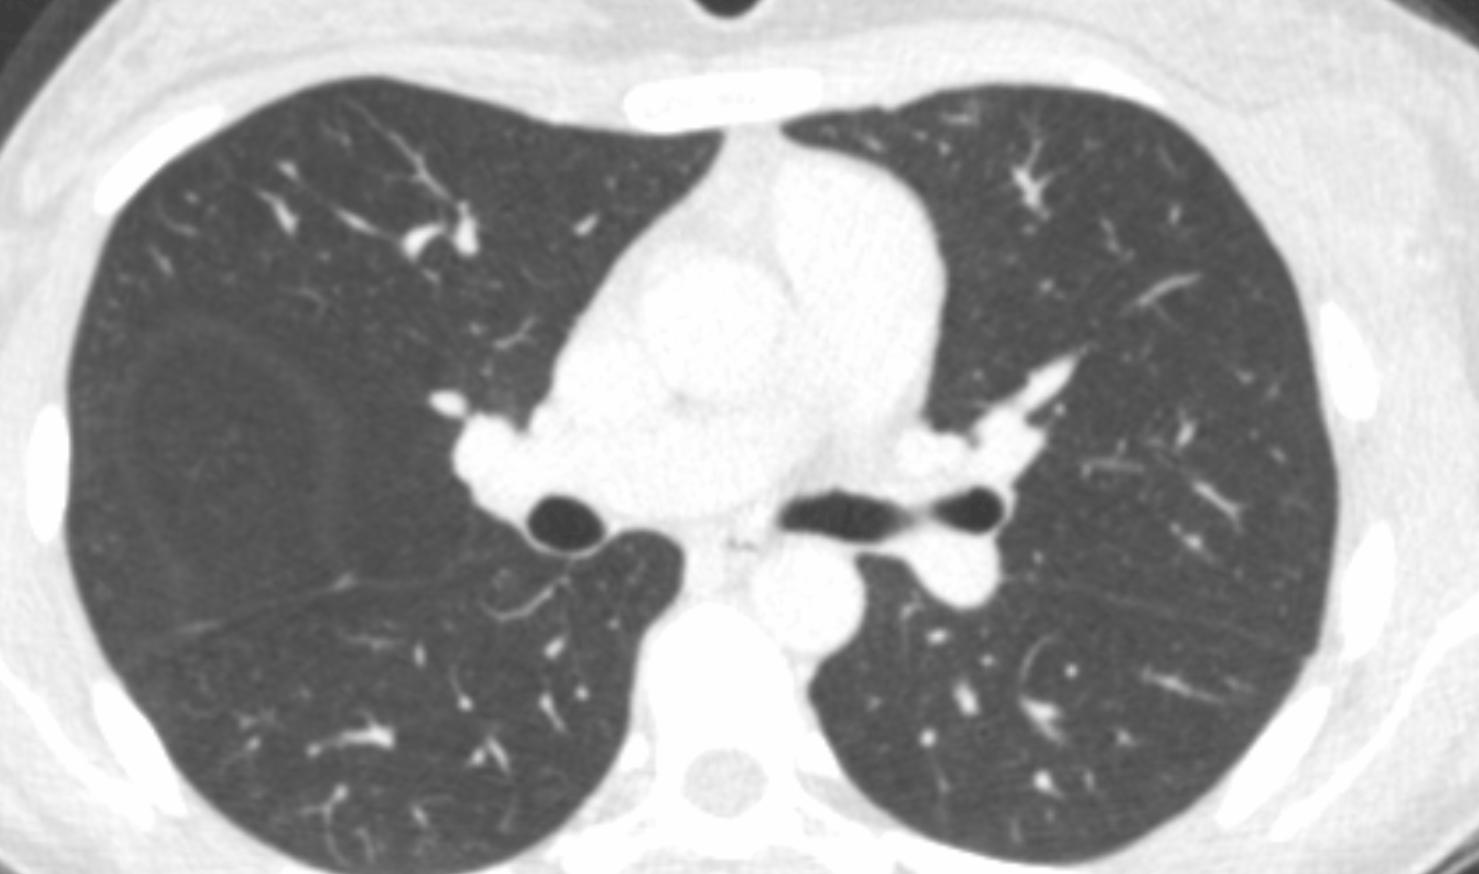

真的如此,且看动态的CT影像,似乎肺部干净的异于常人,如果不是那乳房后方肋骨内外的肿块,没有谁会想到没有丝毫的低热、畏寒、盗汗......毫无症状的年轻人真的有了疾病!